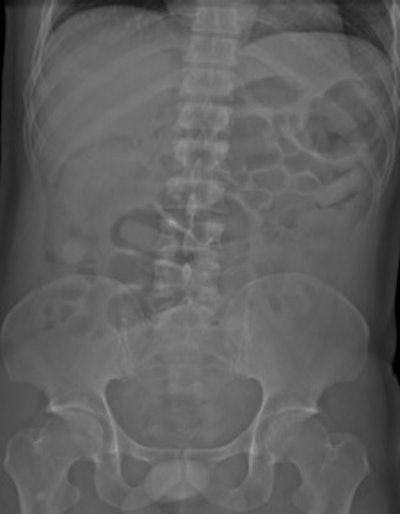

Top left: Low-dose linear slit digital radiography (LSDR) of a typical body packer with 145 intracorporal packs along the alimentary tract. Bottom left: Magnified view of the packs. Note the radiolucent rim within the periphery of the packs due to air trapping creating the so-called "double-condom sign" and "halo sign." Top right: DR of a typical body packer with 83 cocaine packs in the gastrointestinal tract. Bottom right: Note the longitudinal packs (weight approximately 10 to 12 g) projecting over the colon. The magnified view depicts the typical "double-condom sign" due to inevitable air trapped within the wrapping layers during manufacture.DR and low-dose linear slit digital radiography exams were less accurate. CT exams had an overall accuracy rate of 97.1%, followed by DR (71.4%, and 60% for low-dose linear slit digital radiography).